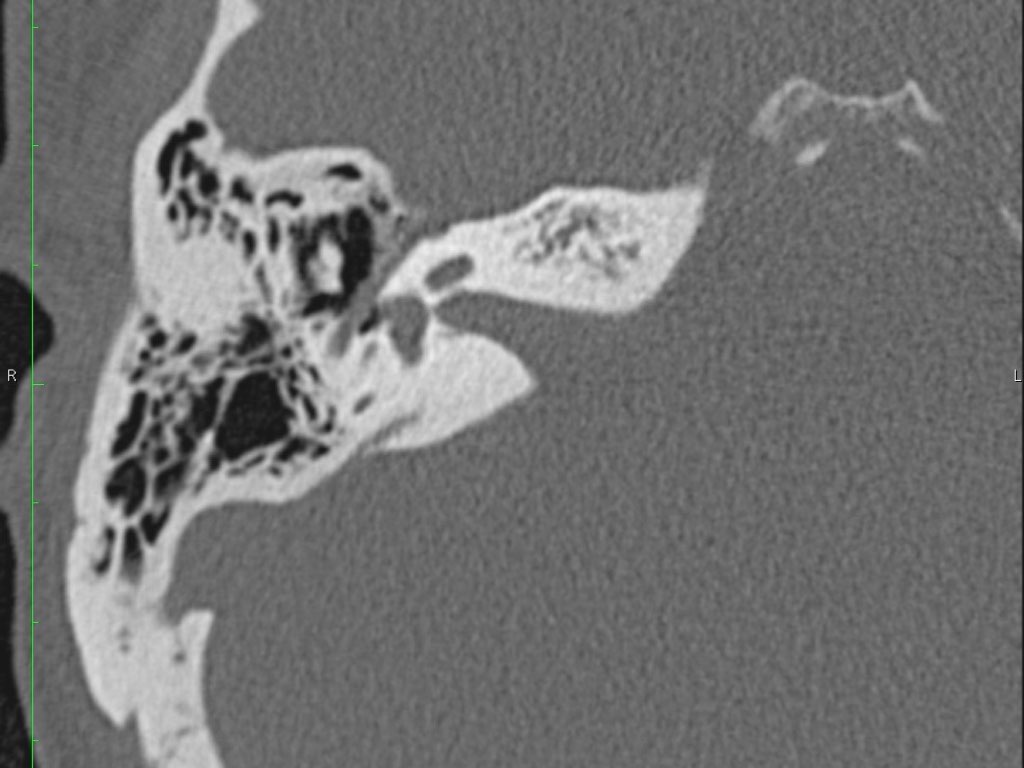

Giải phẫu mặt phẳng coronal của xương đá

Nhấp vào hình ảnh để phóng to.

Cuộn qua các hình ảnh.

Chuỗi xương con

Trong nhiều hình minh họa, xương đe thường được vẽ kết nối về phía trong với xương búa, tuy nhiên điều này không chính xác.

Trên ảnh tái tạo mặt phẳng coronal bên trái, có thể thấy rõ ràng rằng xương đe nằm ở phía sau ngoài so với đầu xương búa.

Ngành dài của xương đe sau đó chạy xuống dưới và vào trong để tiếp khớp với xương bàn đạp.